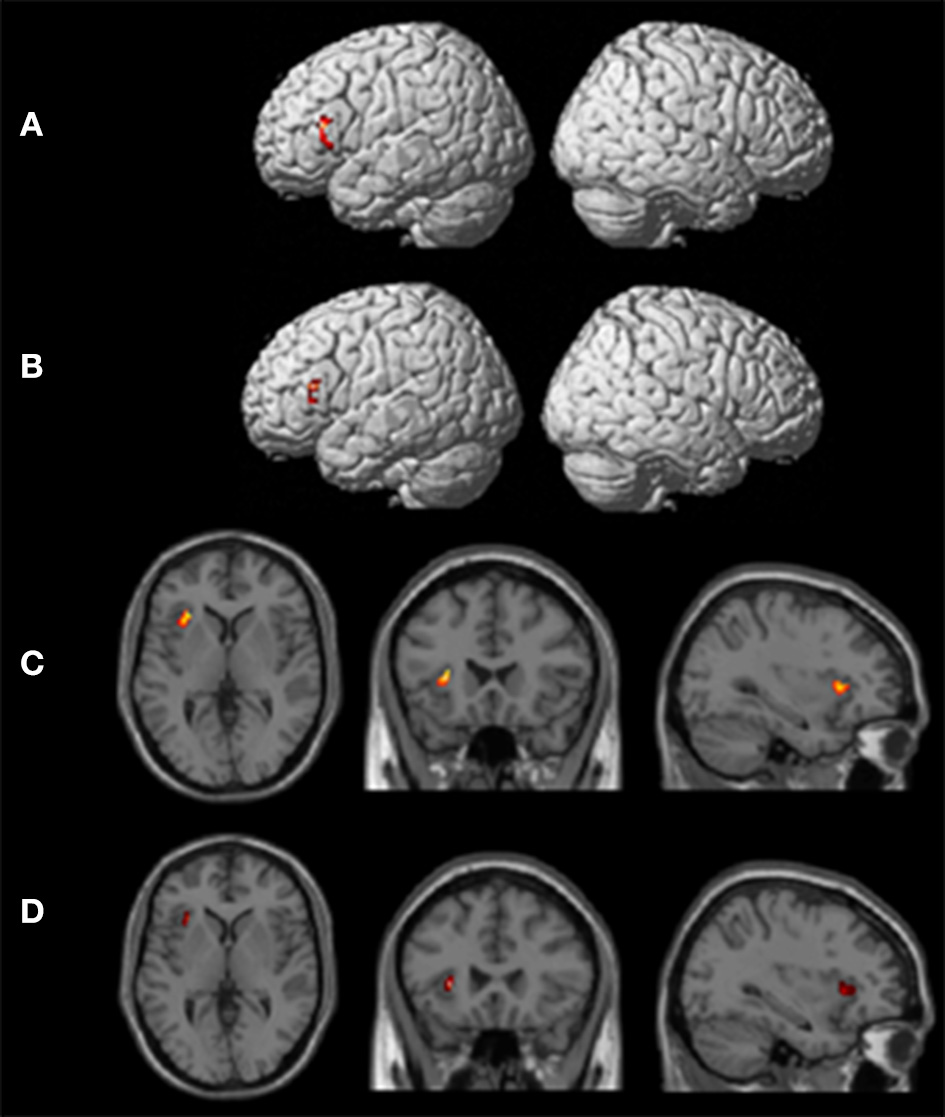

Group Analyses

One-sample t-tests of first-level contrasts revealed a significant cluster situated within left pars triangularis during backward translation (Figure 3A and Table 5). By contrast, forward translation was associated with increased activity in a region situated within the left anterior insula (Figure 3C and Table 5). These results did not change when modeling age as a covariate (Figures 3B,D and Table 5).

Figure 3. Results of the group analyses. Significant results for the the linear contrasts “translation L2 to L1” vs. “shadowing L2” (A,B) and “translation L1 to L2” vs. “shadowing L1” (C,D) are shown on rendering surfaces (A,B) as well as on transversal (left), coronal (middle), and sagittal (rigth) brain slices (C,D). The intersecting planes correpond to the coordinates depicted in Table 5. (A,C) represent group analyses without covariates, (B,D) reflect the same contrast with age as covariate.

Table 5. Peak maxima of group results for the contrast “translation L2 to L1” vs. “shadowing L2” and “translation L1 to L2” vs. “shadowing L1” both with and without age as covariate.